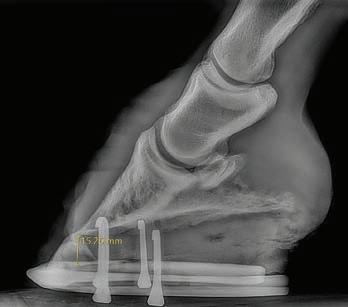

Trimming and farriery

Correct hoof balance is crucial. Therapeutic trimming and appropriate shoes or boots may help relieve strain on the suspensory ligaments. Look for a farrier experienced in managing biomechanical disorders, who understands the importance of balancing both toe length and heel angle.

Why what’s under your horse matters

When a horse moves, every step transfers the loading force up the leg. The hoof is the first structure to hit the ground, and the way it is shaped, balanced, and maintained determines how that force travels through tendons, ligaments, and joints. Get it right and you’re protecting some of the most injury-prone tissues in the horse’s body. Get it wrong and you could be quietly adding strain to structures like the deep digital flexor tendon and the suspensory ligament until one day they fail. How does hoof balance change tendon and ligament strain?

Excess toe length

When the toe grows too far forward, the hoof takes longer to roll forward and leave the ground. This stage is known as breakover, and when it is delayed the tendons and ligaments work harder with every step. This forces the deep digital flexor tendon and suspensory ligament to work harder to lift the limb. Over time this adds fatigue and increases injury risk.

Low or collapsed heels

When the heels are too low and the back of the foot lacks strength in the digital cushion and collateral cartilages, the hoof sinks more with each step. This puts extra stretch and strain on the tendons and the structures that support the fetlock. The right amount of heel support, when needed, can help take the pressure off tendons and ligaments.

The suspensory ligament’s main function is to support the fetlock and stop it from overloading and dropping too far toward the ground when the horse is in motion. Any hoof shape or landing pattern that increases fetlock extension such as long toes, underrun heels, or negative palmar angles pushes more load into this structure. In horses recovering from a suspensory injury, correcting hoof mechanics is essential. Without it, rehabilitation stalls or reinjury is almost inevitable.

What therapeutic trimming really means

Therapeutic trimming is a deliberate approach to restoring correct hoof pastern alignment, shortening the toe lever, bringing breakover back under the centre of rotation, and building a strong supportive heel base and frog for a heel first landing. It also addresses side-to-side imbalances so both branches of the suspensory share the load evenly. Changes are maintained with shorter trim or shoe cycles, often every four weeks. Each time your hoof care professional visits, their goal is to keep the hoof in correct form and function (or be constantly working towards this in rehab cases). This is why engaging a qualified professional who can work on a consistent, short cycle is such an important part of whole horse health. Therapeutic hoof care may involve shoes or composite materials, boots and pads, or leaving the horse barefoot. The method matters less than achieving the right mechanics, choosing what is best for your horse, and matching it to your ability to maintain the hooves between professional visits. Why the right hoof care professional matters

A qualified hoof care provider has the training to read the hoof, assess the horse in motion, and make changes that improve comfort and balance without over correcting.

They can spot subtle imbalances before they cause injury, work alongside vets and assess radiographs for precise adjustments. They can help recognise hoof pathologies such as deep thrush that silently change gait and load patterns, and tailor the trim or shoeing package to the horse’s discipline, workload, and recovery stage.